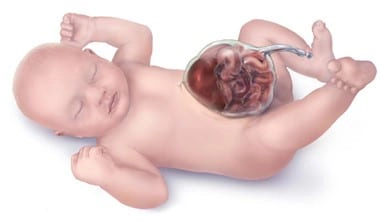

Hở thành bụng thai quý I (Gastroschisis)

16/03/2026